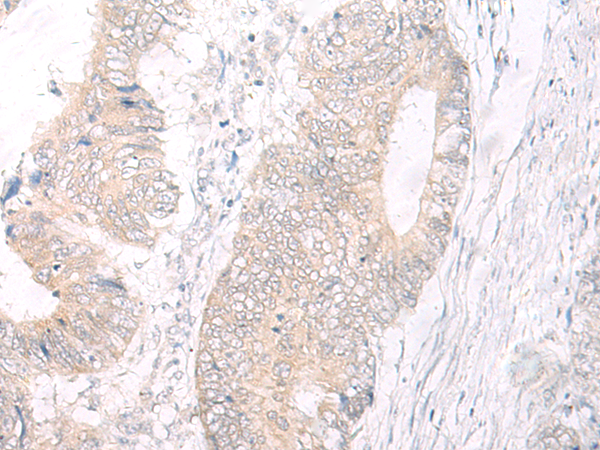

ELISA, IHC |

IL17A |

IHC positive control: |

Human colorectal cancer |